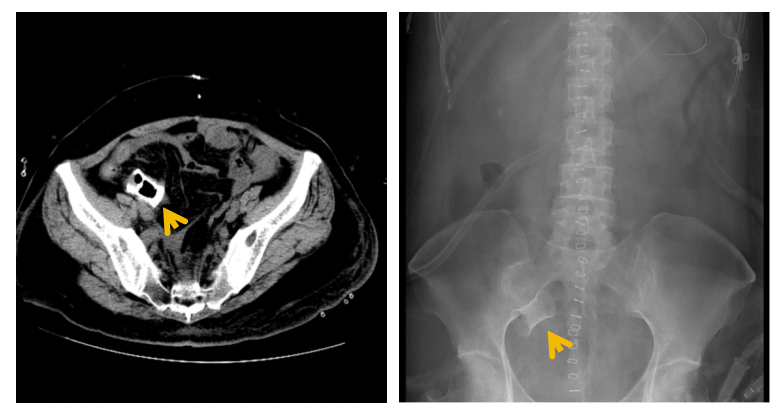

在妇科肿瘤外科、营养科及护理团队的通力合作下,患者邓女士术后恢复迅速,顺利进食,转流管引流通畅。术后复查显示支架位置良好,肝肾功能等指标稳定,并于术后第三周如期开始了首次静脉化疗。术后第四周,影像学证实支架已完全降解,转流管成功拔除,患者进食半流质后一切正常,吻合口愈合良好(如图4)。

图4:术后腹部平片可见小肠支架完全降解(左)/肠道造影发现吻合口愈合良好(右)

(图源:浙江省肿瘤医院)